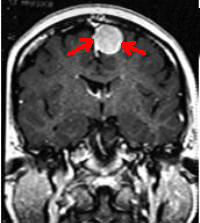

图 核磁图像见脑顶部脑膜瘤